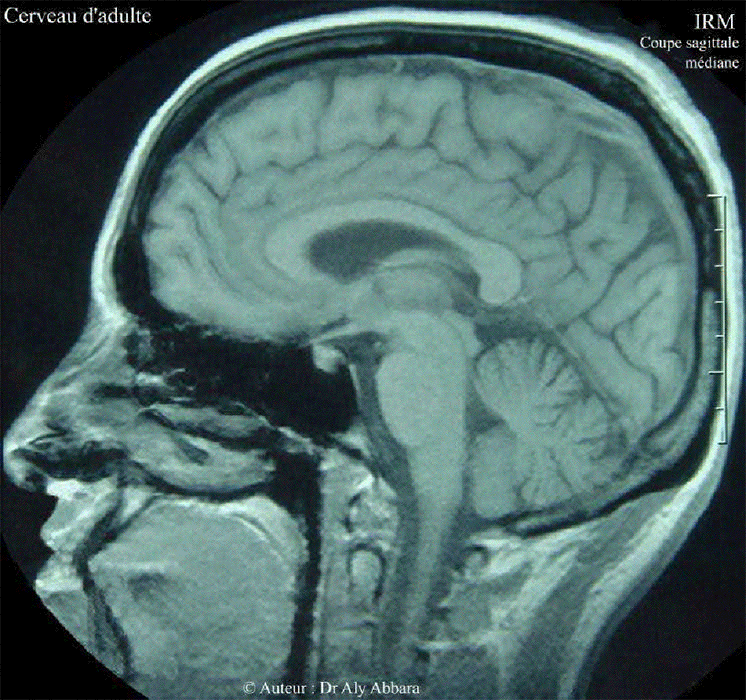

Série animée de coupes sagittales en IRM (AAHscout) montrant l'ensemble du cerveau normal chez une femme âgée de 26 ans

Série animée de coupes sagittales en IRM (AAHscout) montrant l'ensemble du cerveau normal chez une femme âgée de 26 ans.